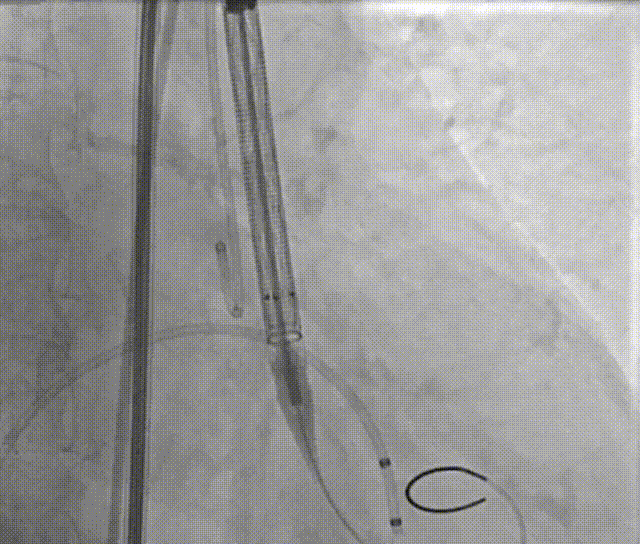

手术过程